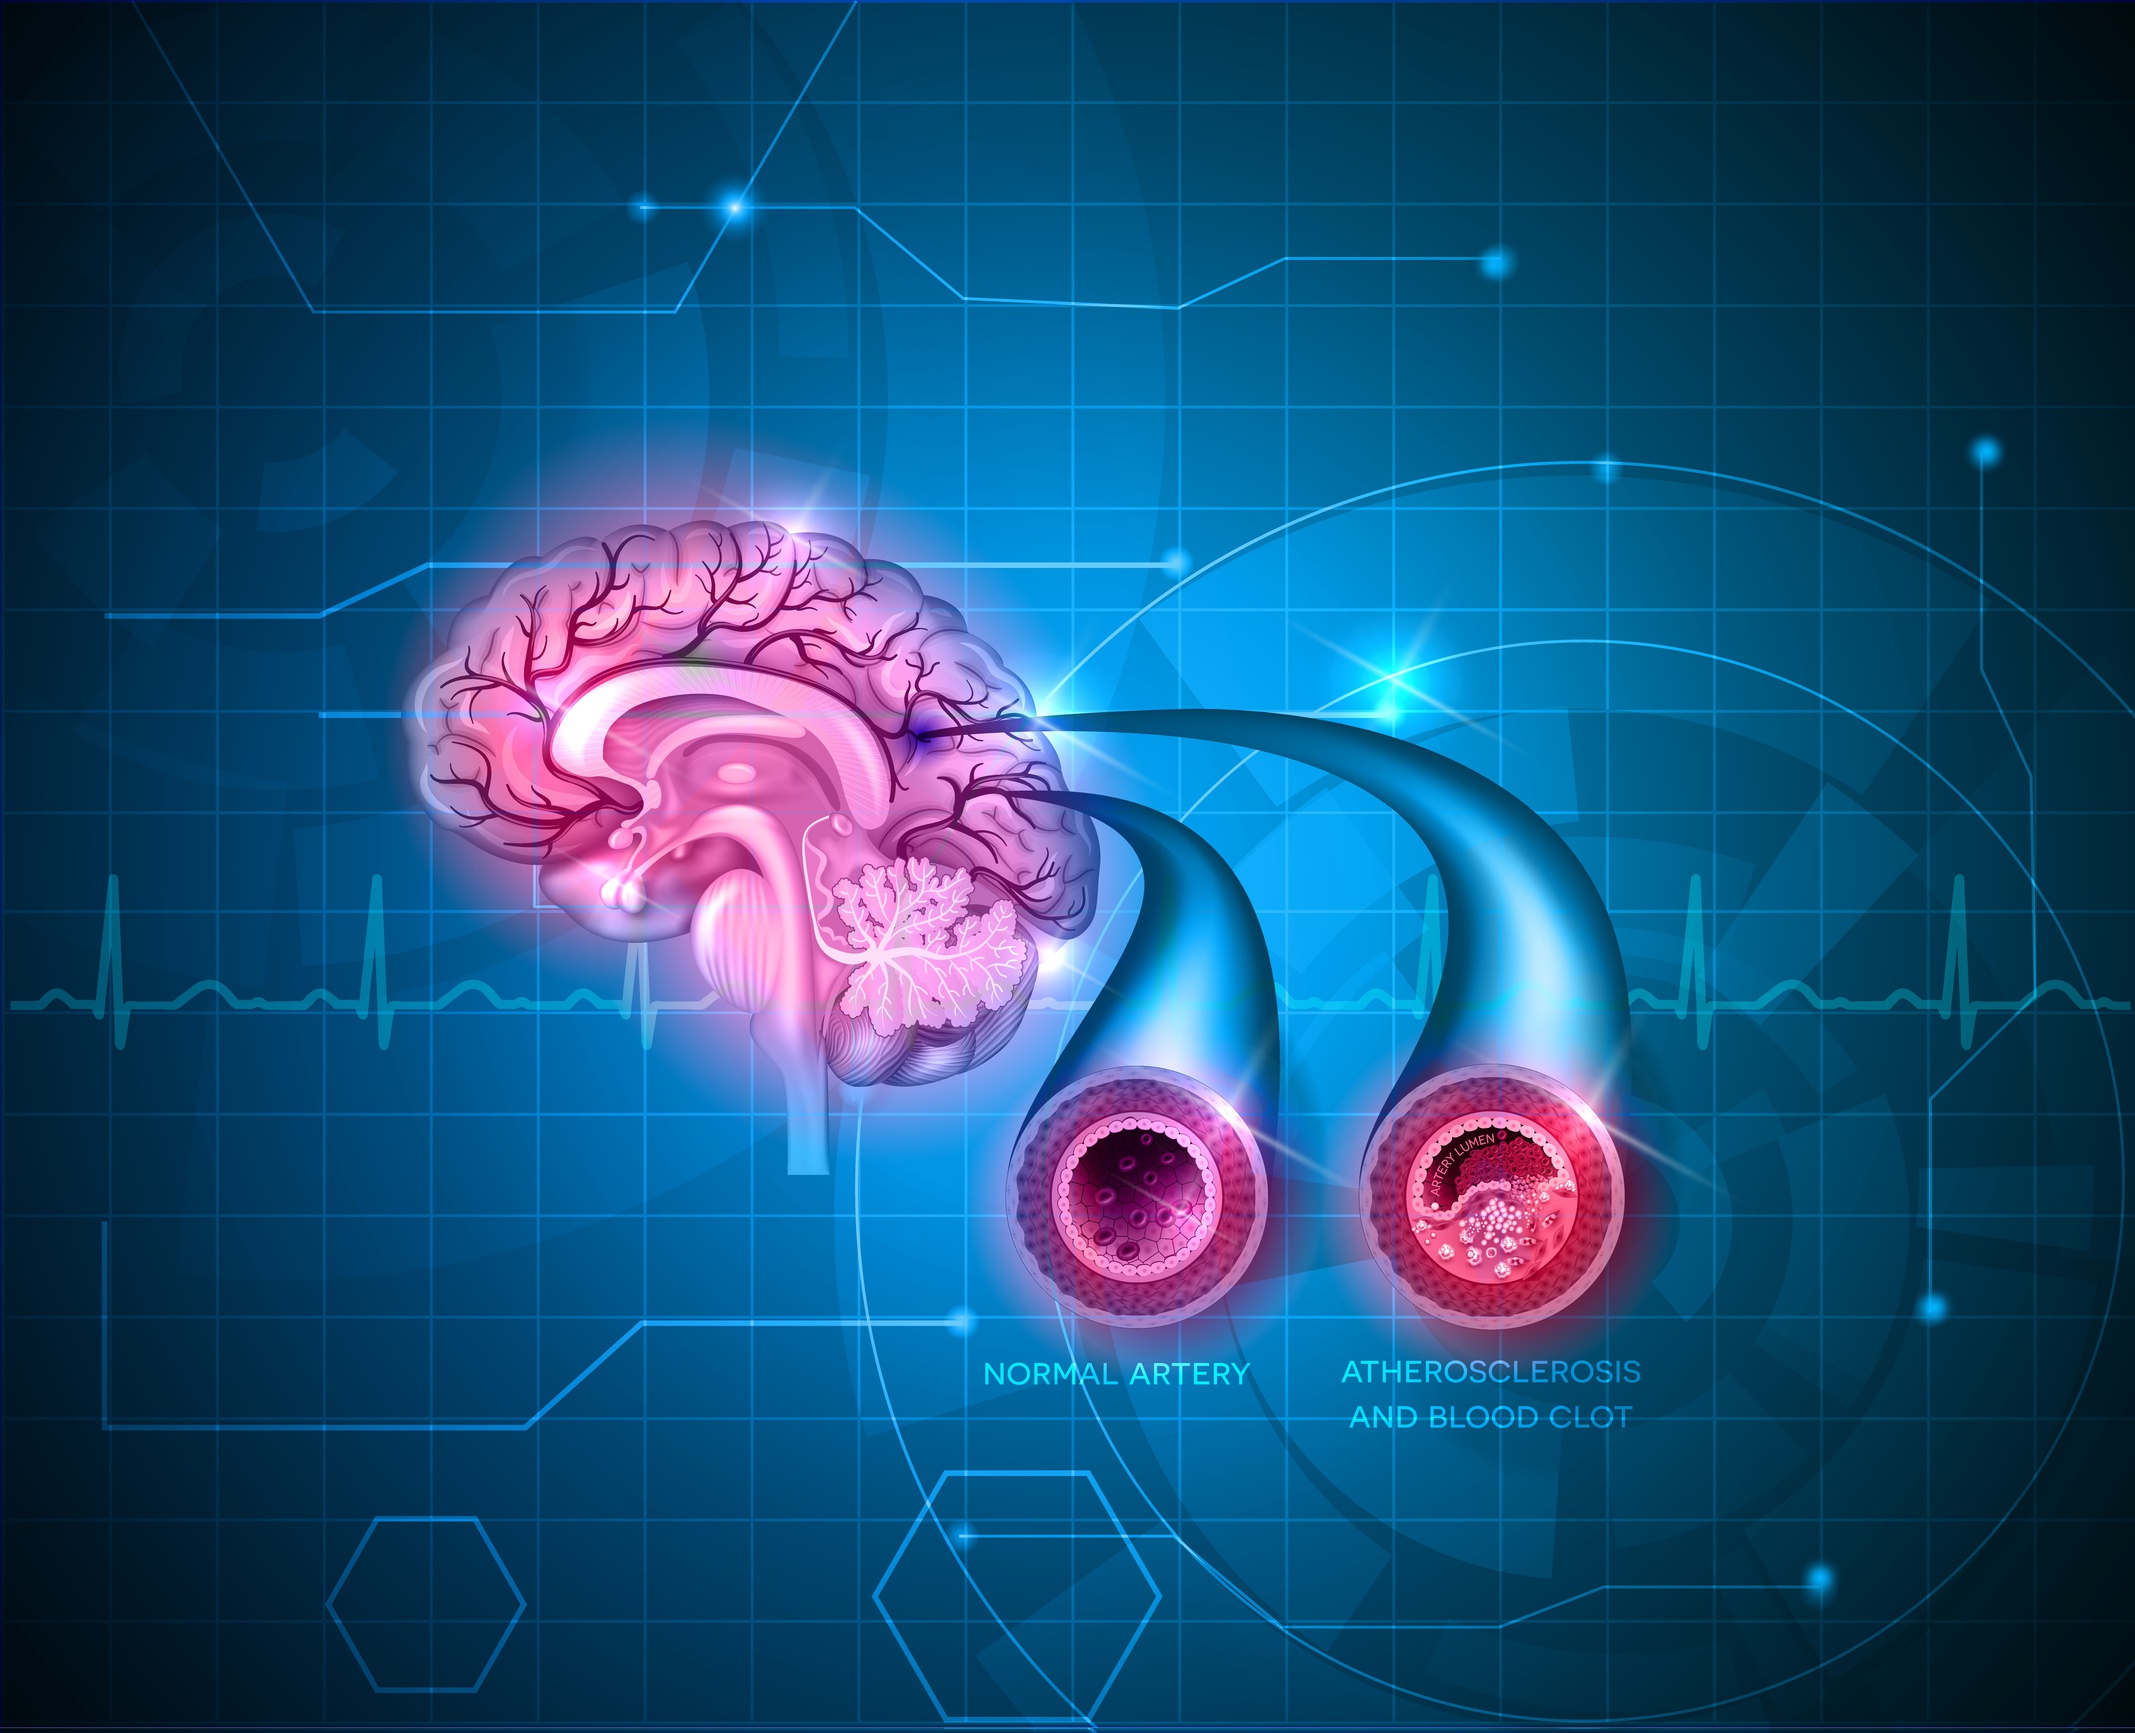

The trial included 3533 non-demented adult patients (70-78 years old), but the majority of the group had ben assessed as having one more risk factors associated with cardiovascular disease risk. The attendant care focused on the treatment of diabetes, hypertension, elevated cholesterol, weight reduction, smoking cessation and active exercise.

Preliminary reports at the two year mark showed a twofold reduction of blood pressure in the intervention group versus the control group.

A 6-year follow-up will assess whether “nurse-led intensive vascular care in primary care decreases the incidence of dementia and reduces disability”.(8) Brain atrophy rates as monitored by MRI will be included the final report.

Coronary artery disease restricts blood flow to the brain and increases the risk for stroke, vascular dementia, and Alzheimer’s

The risk for dementia is set in motion by a host of genetic and environmental risk factors that are prominent at mid-life. The neuropathology of vascular dementia and late-onset Alzheimer’s disease begins years and perhaps decades before a more prominent disease process is noticeable or before it is diagnosed, and cardiometabolic risk factors are center stage to in the timeline of the disease process.